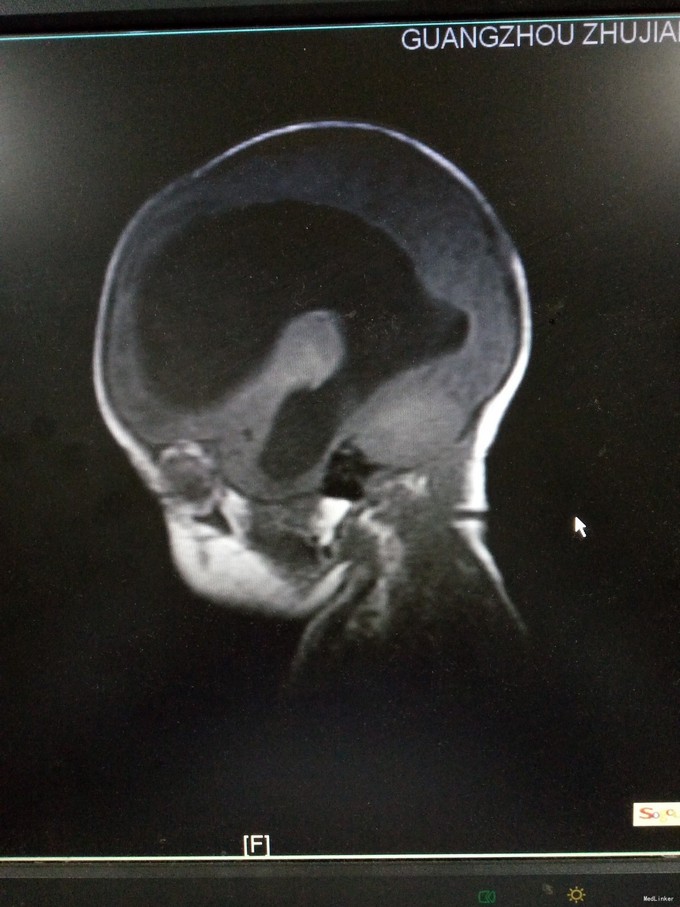

患儿男,29天,因“抽搐1天”入院。患儿足月顺产,出生时无明显异常。其母亲自诉孕期产检无特殊。

查体:发育正常,神清,反应欠佳。前囟3.5*3.5cm,隆起,张力稍高,颅缝分离约0.5cm。双肺呼吸音粗糙,心腹未及明显异常。四肢肌张力稍高,生理反射可引出,病理反射未引出。入院后完善颅脑CT、腰椎穿刺术等,结果如下。

初步诊断为:1.交通性脑积水;2.化脓性脑膜炎。入院后予美罗培南抗感染、营养脑神经、维持内环境平衡等治疗。请神经外科会诊后建议行脑室-腹腔分流术。经近2周治疗后,患儿症状有好转,但病情尚不稳定,家属要求出院,予签字出院。